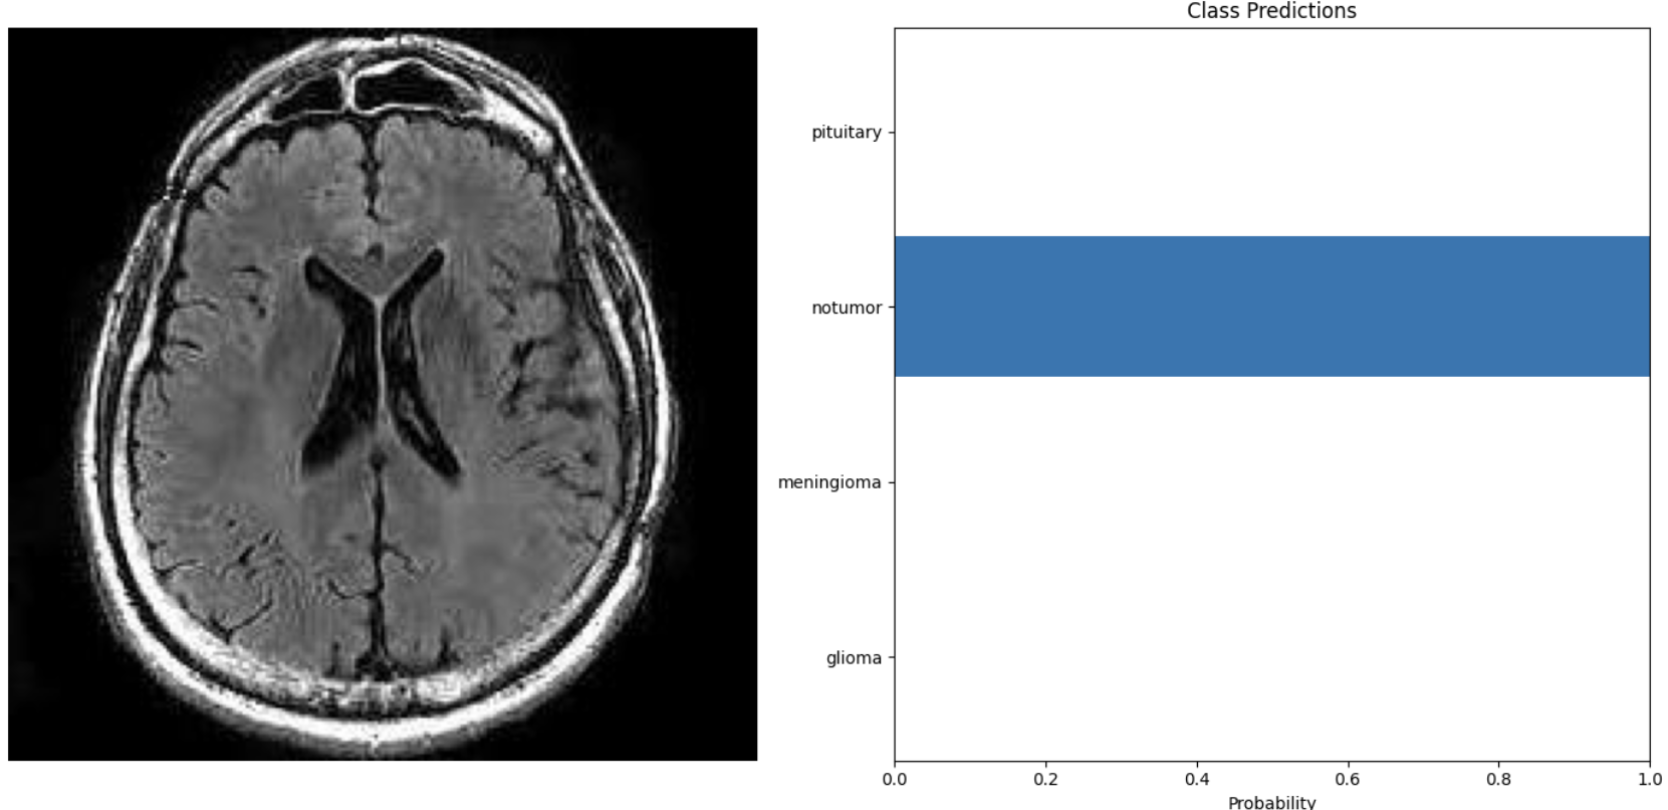

MRI Image MRI Image

Just like humans have certainty when answering questions, my model's output is a representation of how confident it is in its answers. The two images on the right are what my program outputs when prompted with an image. The MRI scan is the test image, and the graphs show its certainty in the answers. The top image shows a certain prediction. In this guess, the blue bar shows that the model is 100% certain that there is no tumor in the MRI scan. Compared to the bottom photo, the model is guessing a few different types of tumors.

After training my model on the 5000 images, I ran through a testing set. Testing set images come from the same source as the training set. Although they are different images, they will be of the same style and quality as the training. I ran through 10 testing images, and they were all predicted accurately with nearly 100% certainty in all of the responses. This shows that AI has the capability of diagnosing tumors with very high accuracy and speed when trained properly.